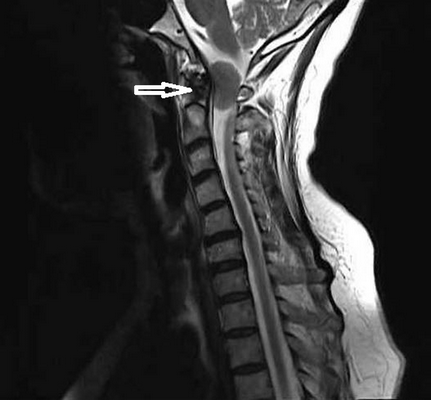

Опухоль краниовертебральной области (обозначена стрелкой)